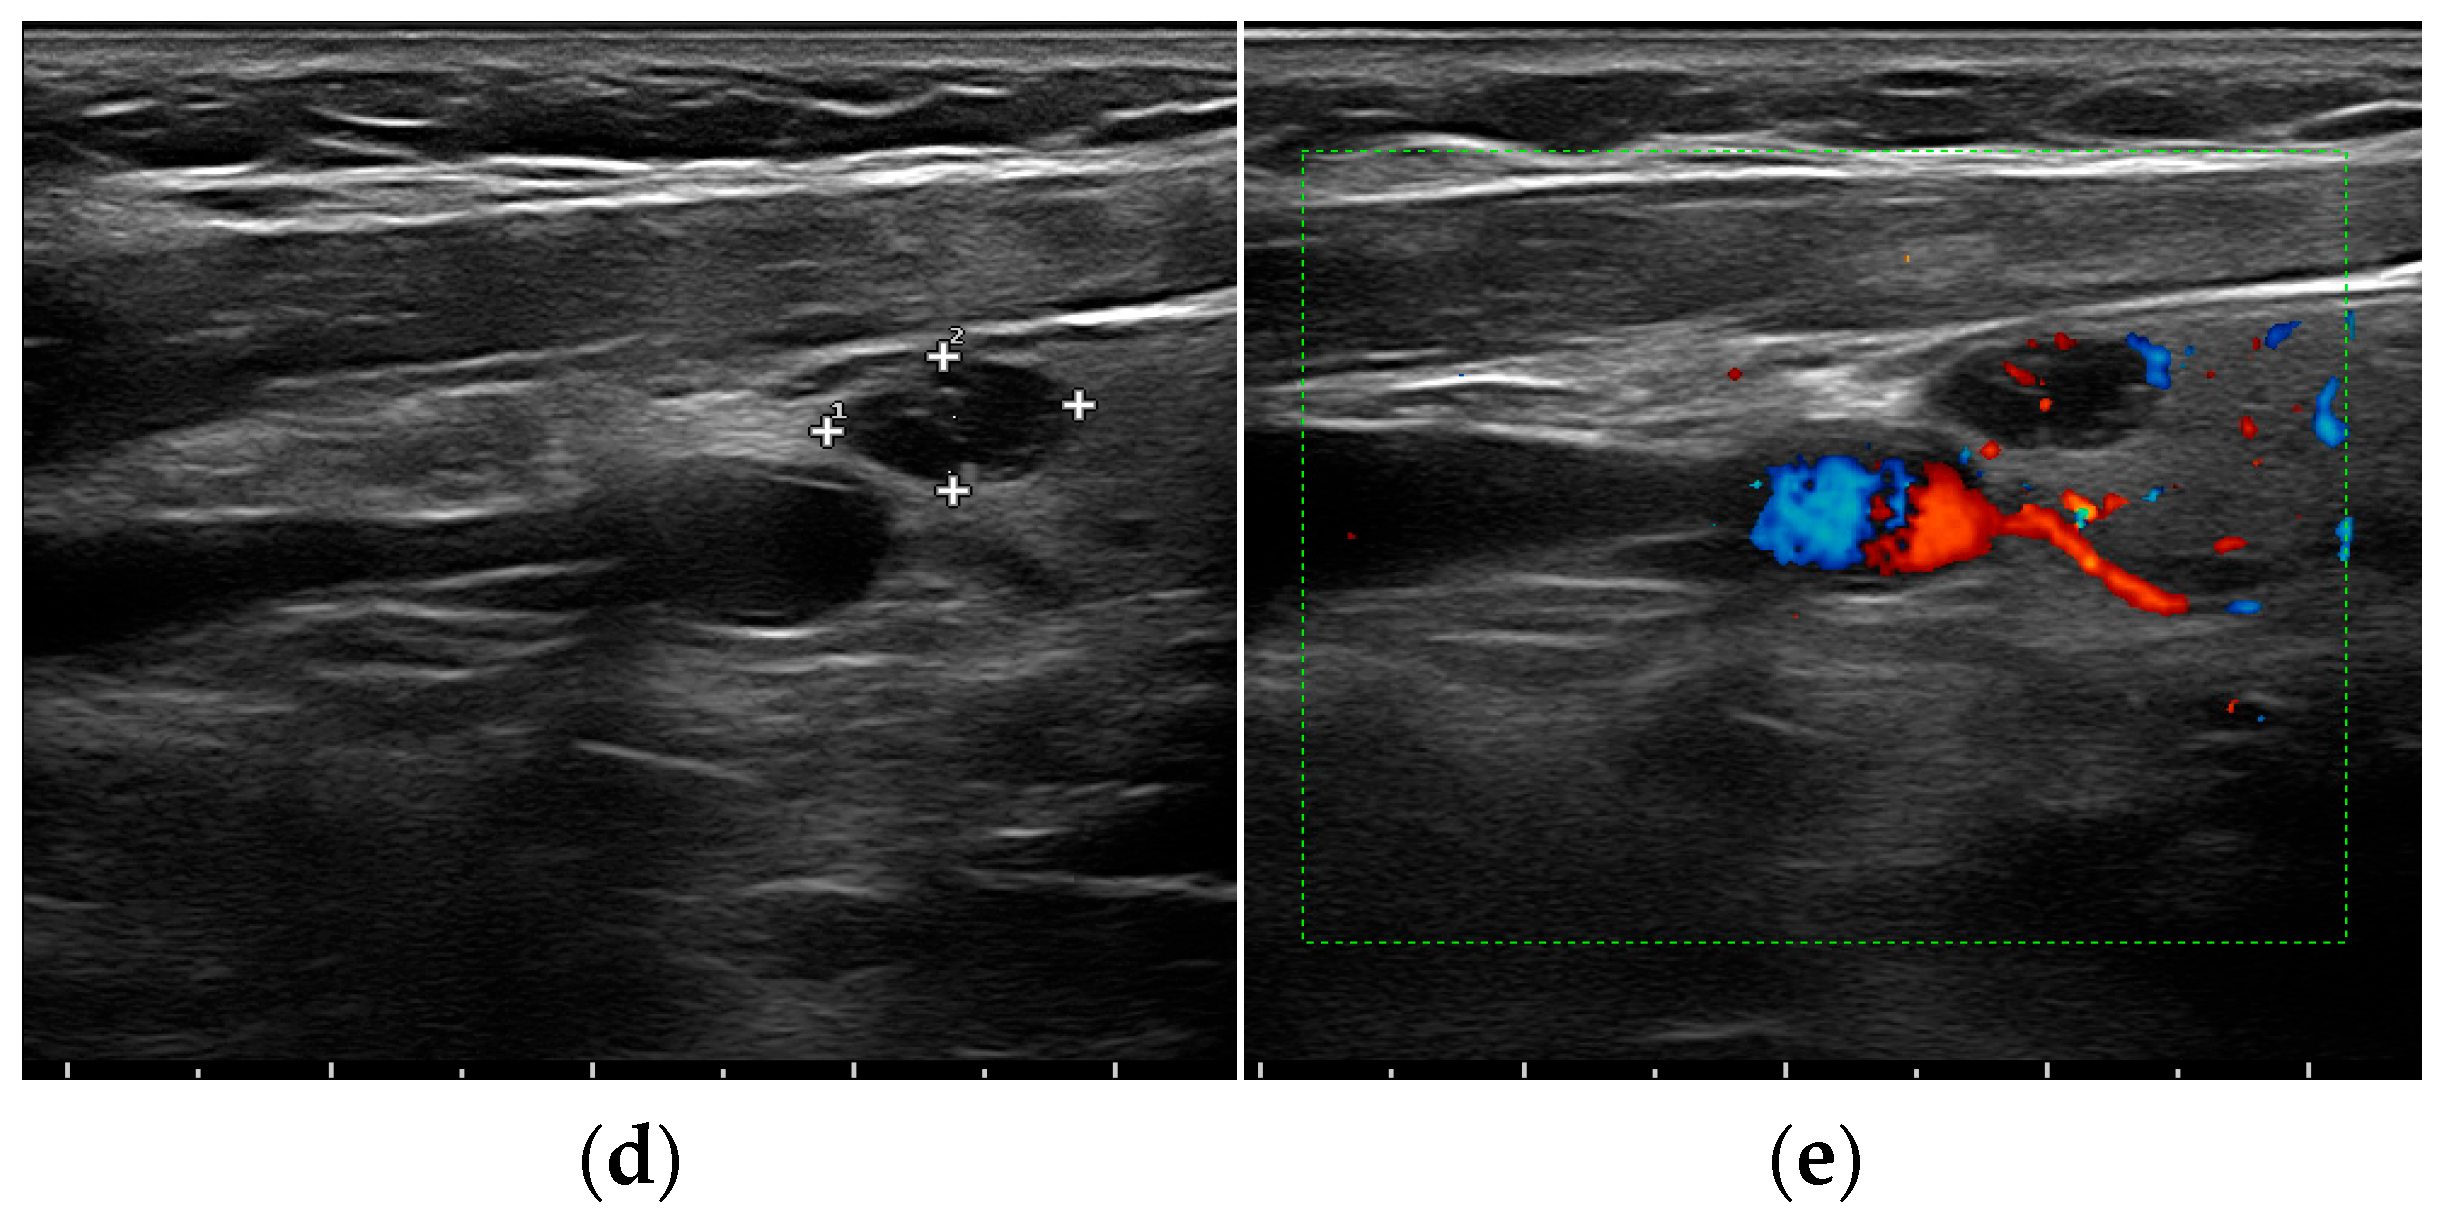

- Mohammadi, A.; Moloudi, F.; Ghasemi-rad, M. The role of colour Doppler ultrasonography in the preoperative localization of parathyroid adenomas. Endocr. J. 2012, 59, 375–382. [Google Scholar] [CrossRef]

- Vitetta, G.M.; Ravera, A.; Mensa, G.; Fuso, L.; Neri, P.; Carriero, A.; Cirillo, S. Actual role of color-doppler high-resolution neck ultrasonography in primary hyperparathyroidism: A clinical review and an observational study with a comparison of (99m)Tc-sestamibi parathyroid scintigraphy. J. Ultrasound. 2019, 22, 291–308. [Google Scholar] [CrossRef]

- Liu, H.; Liao, Q.; Wang, Y.; Hu, Y.; Zhu, Q.; Wang, L.; Liu, Q.; Li, J.; Jiang, Y. A new tool for diagnosing parathyroid lesions: Angio plus ultrasound imaging. J. Thorac. Dis. 2019, 11, 4829–4834. [Google Scholar] [CrossRef]

| Parathyroid hyperplasia | More than one symmetrically or asymmetrically enlarged, hypoechoic, oval shaped, lobulated gland. Significantly smaller than adenoma. Cystic inclusions may be seen. | Feeding polar vessels entering the pole and then extending around the periphery. | Fast intense homogeneous enhancement. Fast homogeneous wash-out. | Stiffer than proper parathyroid glands. |

| Parathyroid adenoma | Enlarged, circumscribed, hypoechoic, oval shaped lesion, delineated by hyperechoic halo. Cystic inclusions may be seen. | Feeding polar vessels entering the pole and then extending around the periphery. | Early peripheral hyperenhancement. Central wash-out in the later phases. | Stiffer than hyperplastic parathyroid glands. |